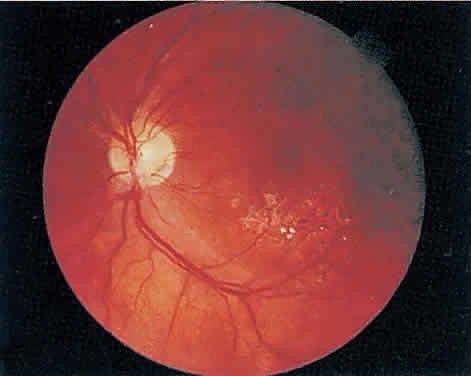

The hallmark lesion of CMV retinitis is a necrotizing, full-thickness retinitis that results in retinal cell destruction. CMV often initially affects retinal tissue adjacent to major retinal blood vessels or the optic disc (Fig. 1). This is consistent with the concept that the virus is spread to the retina hematogenously. In most cases, the pattern of infection is classic and distinctive, making clinical diagnosis straightforward. The area of active retinitis has a granular, dirty-white appearance. As the virus attacks the endothelial cells of blood vessels, hemorrhage is common. Advancement in the retinitis by both direct cell-to-cell transmission as well as spread by way of adjacent satellite lesions can be seen. Except for cases in which retinitis is acute, it is common to see areas of healed retinitis beside areas of active necrosis. Areas of burned-out necrosis show absence of any retinal tissue, whereas the underlying retinal pigment epithelium assumes a “salt and pepper” appearance. CMV retinitis can present initially as either large areas of retinal necrosis with hemorrhage or one or more small, focal areas of retinal whitening.1,12,14 These small, focal lesions may on occasion be confused with cotton-wool spots or lesions of toxoplasmosis.5,27 Unlike cotton-wool spots, focal areas of CMV may appear outside the posterior pole. These early, focal infiltrates of CMV may not be associated with retinal hemorrhages or vitreous cells.

Over a course that usually spans weeks, infiltrates of CMV tend to assume two different patterns of clinical disease.11,12 The first pattern is called hemorrhagic and is characterized by broad geographic zones of retinal whitening. These large, geographic lesions are usually in close proximity to a major retinal blood vessel or the optic nerve. Satellite lesions are common. When the retinal necrosis associated with CMV retinitis becomes widespread, it is almost invariably associated with retinal hemorrhages. Although the border between necrotic and unaffected retina is sharply demarcated, the border itself appears irregular and jagged. Exudation into the retina or subretinal space may be seen, adding to the granular appearance of the retinitis. Juxtaposition of large zones of white, granular necrosis with those of red retinal hemorrhage has led this appearance of CMV retinitis to be described as either “pizza-pie” or “cheese and ketchup.” The retinal blood vessels, both arteries and veins, in the areas of necrosis commonly appear sheathed, secondary to a vasculitis. As a consequence, secondary retinal vascular occlusions, especially branch retinal vein obstructions, may occur in the course of CMV retinitis. Immune-mediated vascular damage may play a role in the vasculitis.12 Central healing of these lesions will occur as the infection progresses. Avasculitis resembling “frosted branch angiitis” hasbeen reported (Fig. 2).28 A second pattern of CMVretinitis has been labeled “granular” or “brushfireborder.” In this appearance, the focal granular infiltrates enlarge slowly across a line, leaving ever-increasing areas of destroyed retina and atrophic retinal pigment epithelium behind. Hemorrhages and vitreous cells are a less prominent feature. There appears to be direct cell-to-cell transfer of infected virions in this pattern of infection (Figs. 3 and 4). The brushfire border is commonly seen in CMV retinitis lesions anterior to the equator (Fig. 5). The significance, if any, of these two clinical patterns of CMV retinitis is not known, and, in some eyes, both patterns of disease can be seen simultaneously or in sequence. Progression of retinitis has been defined in clinical trials as movement of a lesion border at least 750 μm along a front that is 750 μm or more in length, development of a new CMV lesion in a previously involved eye or in the uninvolved fellow eye of a patient with baseline unilateral disease.29 Without treatment or improvement in the host's immune system, CMV retinitis is a relentless, slowly progressive infection resulting in blindness caused by total retinal necrosis, retinal detachment, or optic nerve involvement, in any combination.